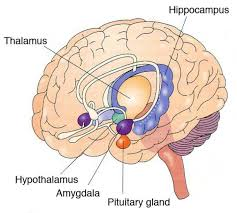

diencephalon

relay station for most sensory and motor pathways, controls visceral activities

diencephalon structures

epithalamus, thalamus, hypothalamus

epithalamus

partially forms roof of diencephalon; covers 3rd ventricle

epithalamus

epithalamus components

pineal gland; habenular nuclei

habenular nuclei

relays signals from limbic system to midbrain; involved in visceral and emotional responses to odor

thalamus

2 halves; sensory impulses from all conscious senses converge on thalamus and synapse and one of its nuclei; made up of about a dozen nuclei

thalamus

hypothalamus functions

control of autonomic nervous system and endocrine system; regulation of body temp; control of emotional behavior; control of food and water intake; regulation of circadian rhythms

infundibulum

connection between hypothalamus and pituitary gland

hypothalamus

limbic system

forms a ring around diencephalon

limbic system functions

structures process and experience emotions; affects memory formation through integration of past memories of physical sensations with emotional states

limbic system